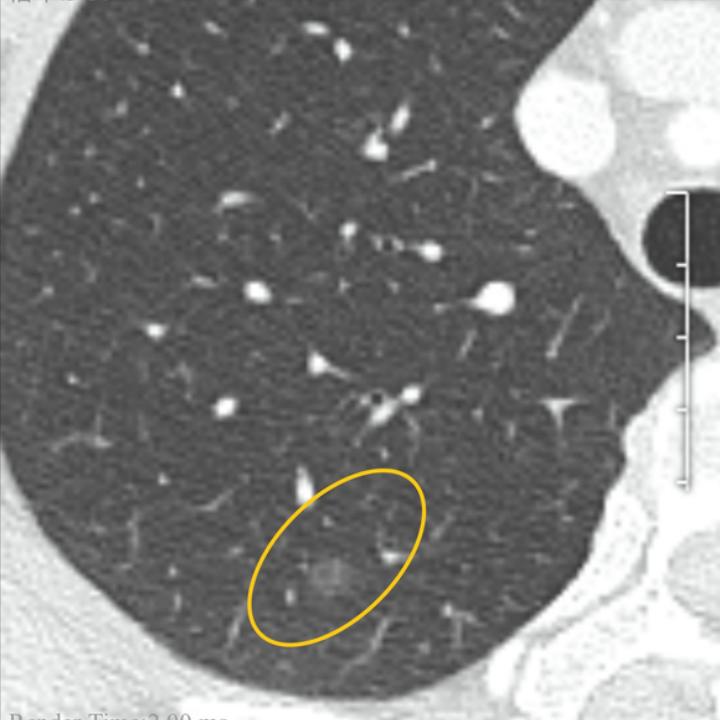

因为爱人刚经历大手术与放疗不敢轻易再进行手术,所以恳请戴主任白忙之中给到看片和答复。也请吧友帮我顶贴,谢谢大家了!,图1,2是2022年12月的pect ct拍的,图3图4是5月19日的片子。拜托了,给大家磕一个。

两侧胸廓对称,右肺上叶后段见不规则磨玻璃密度结节影,边界较清楚,直径约6mm,FDG摄取未见异常。右肺下叶后基底段实性小结节,直径约4mm,FDG摄取未见异常。右侧胸膜钙化灶;两侧胸腔无积液。右肺门、气管前腔静脉后见数枚小淋巴结,部分小钙化灶,大者短径约6mm,FDG摄取稍增高,SUVmax=2.1。

右肺上叶后段磨玻璃密度结节,FDG代谢未见异常,考虑不典型腺瘤样增生可能,建议CT随访复查。右肺下叶后基底段慢性炎性小结节。右侧胸膜钙化灶。右肺门及纵隔数枚慢性炎性小淋巴结,部分伴钙化灶。